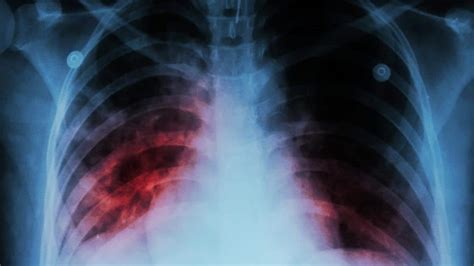

So, you’re experiencing some of those symptoms we just talked about, and you’re wondering, “Okay, how do doctors figure out if it’s actually pulmonary fibrosis ?” Well, it’s usually a process, and it involves a few different steps to rule out other possibilities and confirm the diagnosis. First off, your doctor will want to get a good medical history and do a thorough physical examination . They’ll ask you about your symptoms, how long you’ve had them, your work history, your family history, and any medications you’re taking. During the physical exam, they’ll listen to your lungs with a stethoscope. One of the classic sounds heard with pulmonary fibrosis is called crackles , which sound a bit like Velcro ripping apart, especially at the base of the lungs. If they suspect pulmonary fibrosis , the next step usually involves imaging tests . A chest X-ray can provide a general overview, but it’s often not detailed enough to make a definitive diagnosis. That’s where a high-resolution computed tomography (HRCT) scan comes in. This is a much more detailed scan that can show the characteristic patterns of scarring in the lungs, which is super helpful for diagnosis. Sometimes, imaging alone isn’t enough, and your doctor might recommend pulmonary function tests (PFTs) . These tests measure how well your lungs are working by having you breathe into a machine. They can determine how much air your lungs can hold, how quickly you can inhale and exhale, and how efficiently oxygen is moving into your blood. If the results show reduced lung capacity and impaired oxygen transfer, it further supports the diagnosis of pulmonary fibrosis . In some cases, if the diagnosis is still unclear, a lung biopsy might be necessary. This is a surgical procedure where a small sample of lung tissue is removed and examined under a microscope by a pathologist. This is often considered the gold standard for diagnosis, as it allows for direct visualization of the scarring. It’s a bit more invasive, so it’s usually reserved for situations where other tests haven’t provided a clear answer. Getting a diagnosis can be a journey, but these tools help doctors piece together the puzzle.